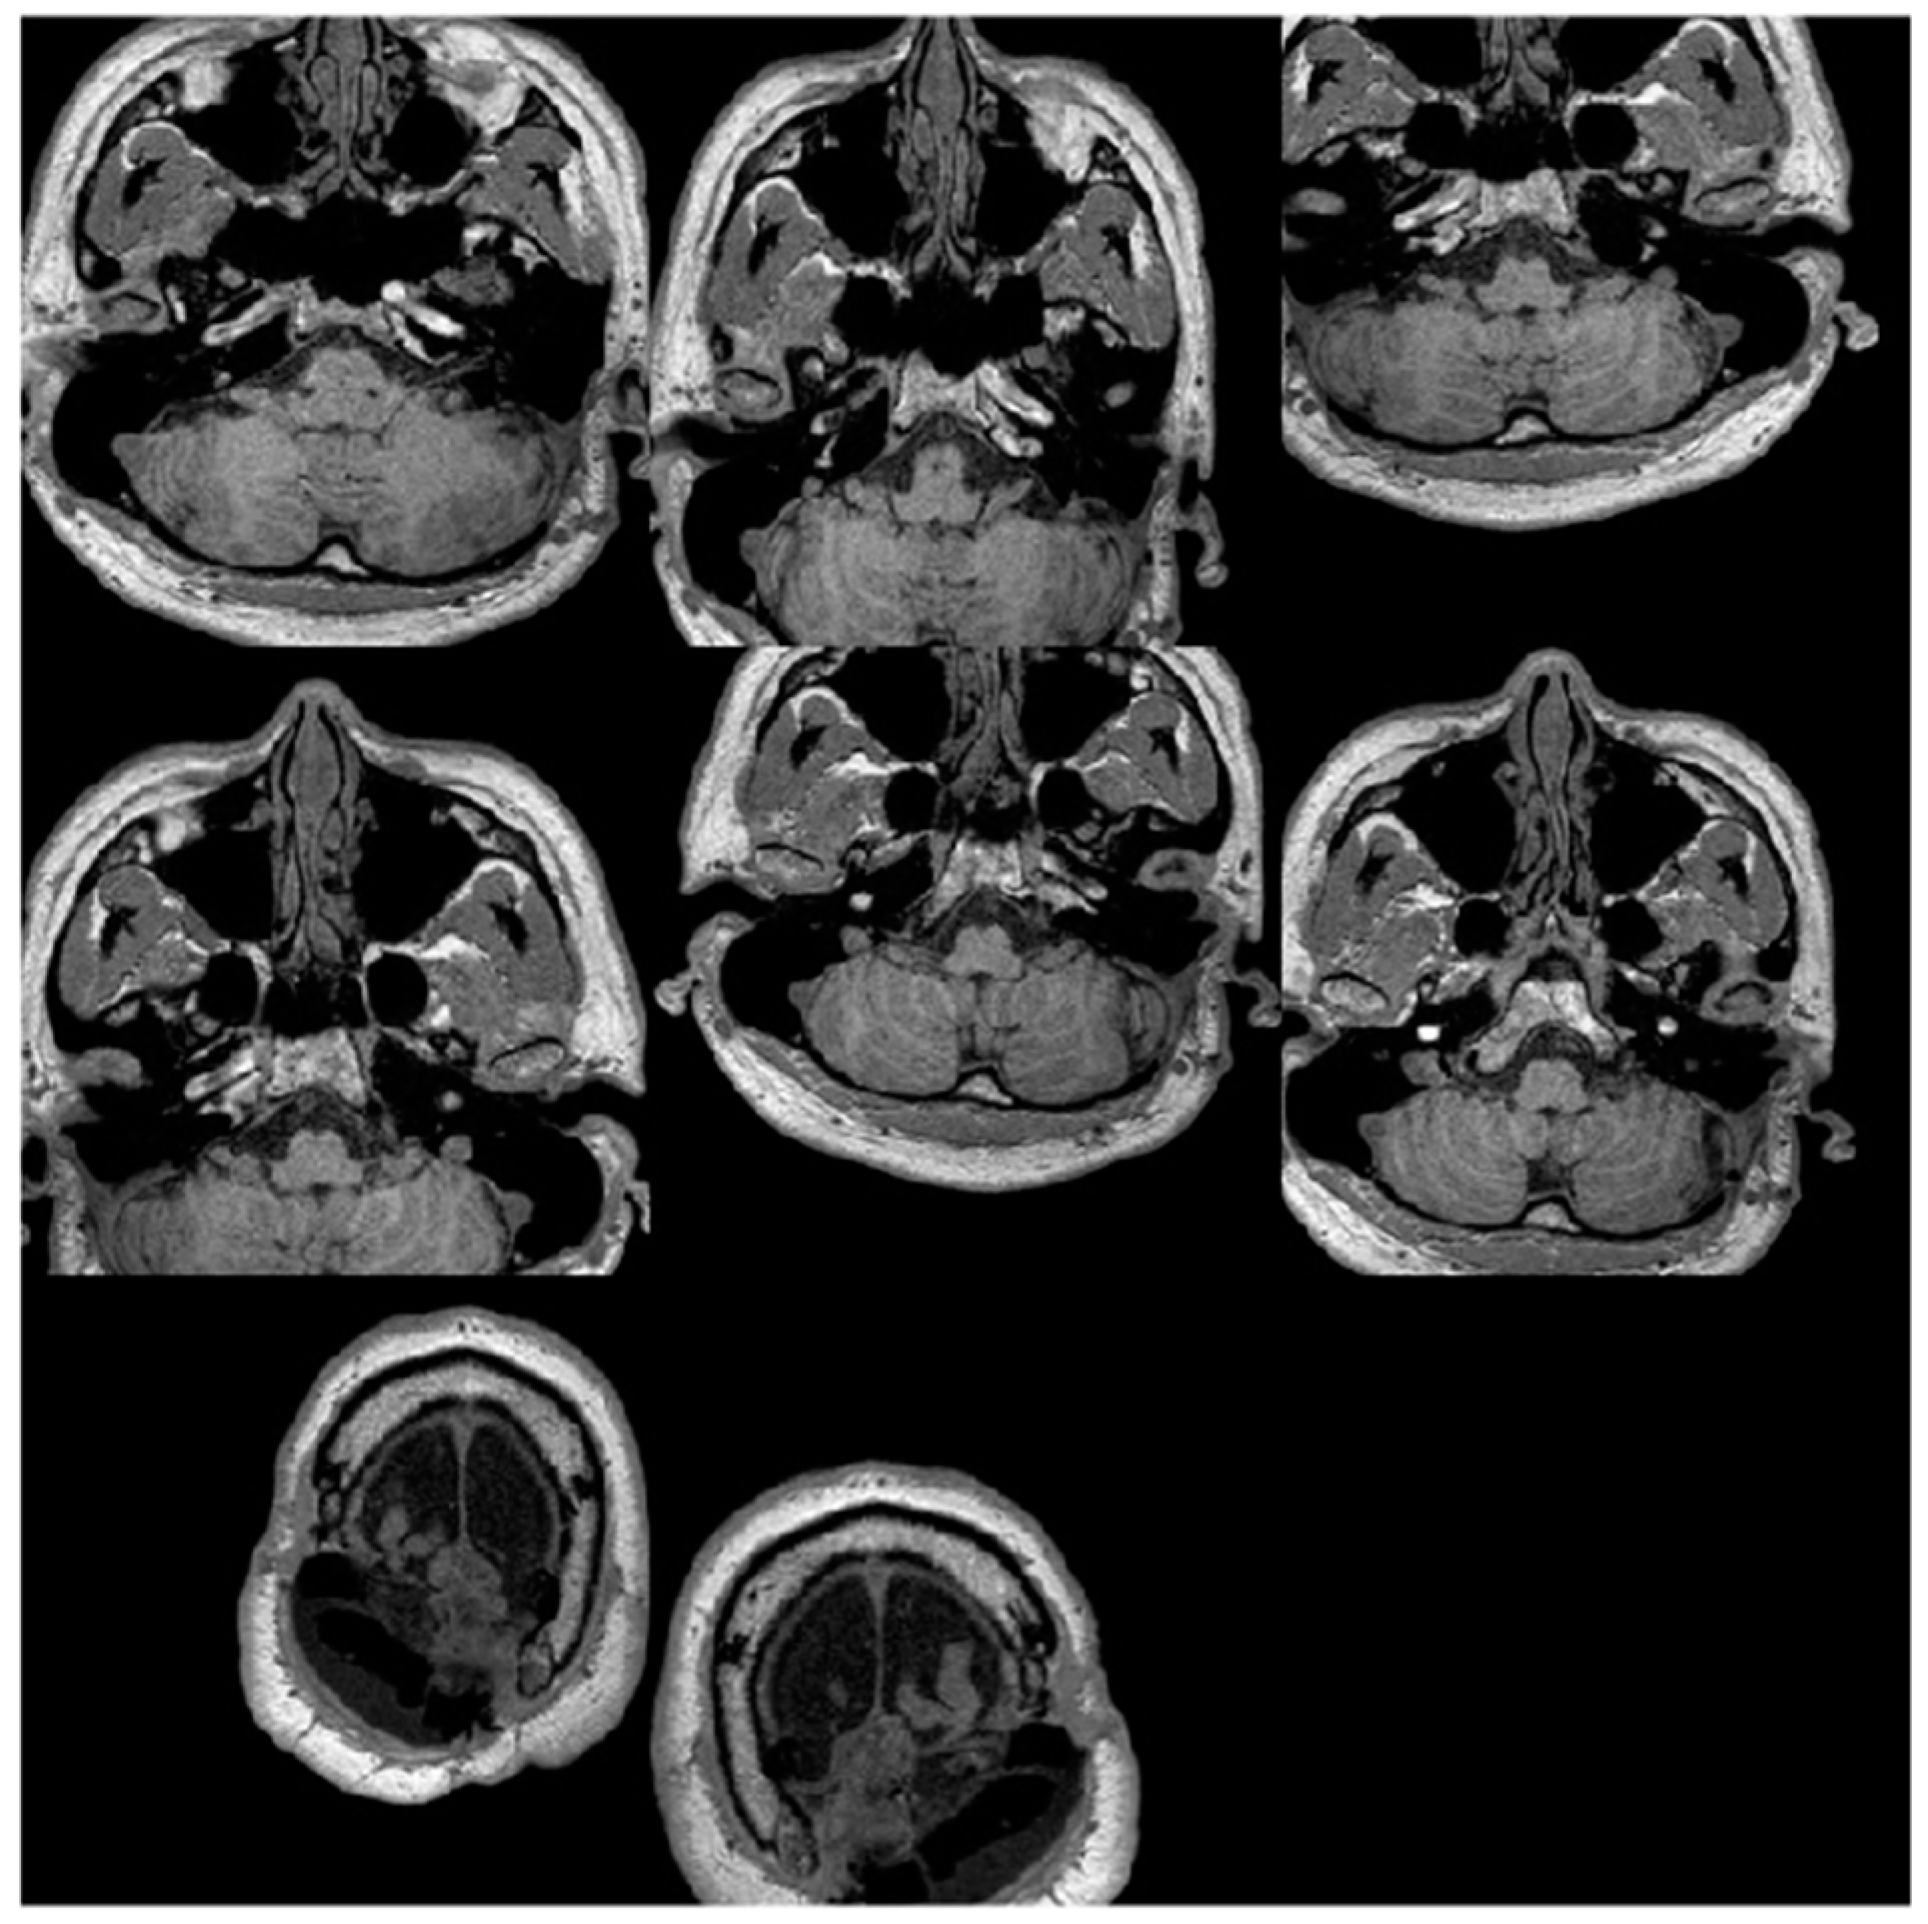

2.1. MRI Dataset

2.4. Dataset Augmentation

3.1. Image Pre-Processing